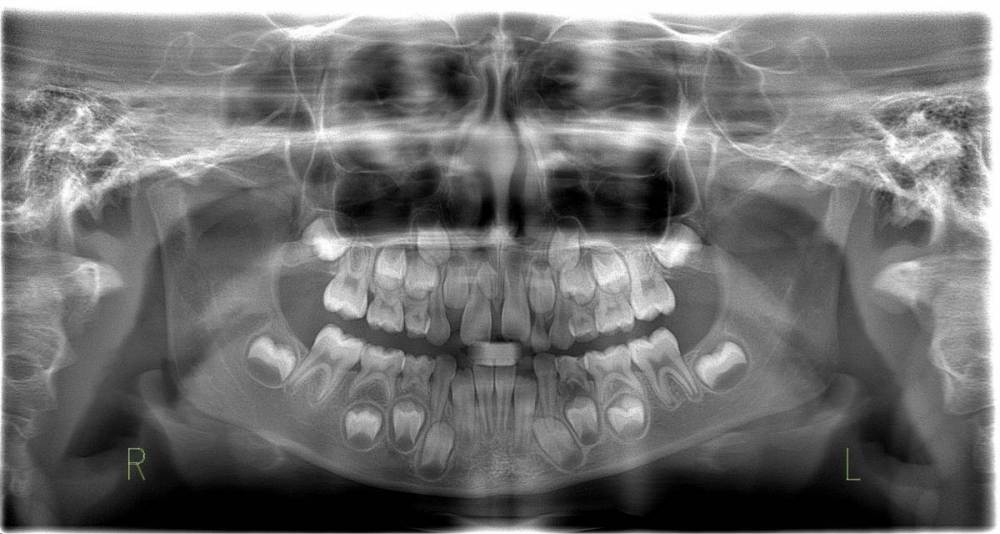

Надо ли удалить молочный 4й зуб (внизу справа). Кариес, но не болит на данный момент. Раньше болел.

Есть переживание что кариес может перейти на постоянный зуб ниже.

Приложил снимок.

Правильно переживаете, там уже не кариес, а периодонтит, то есть удалять или лечить у толкового детского стоматолога, который что- то понимает в лечении каналов молочных зубов. Лечите вовремя кариес, не запускайте.Боль -это не признак нуждаемости в лечении.Это признак того, что вы уже опоздали.